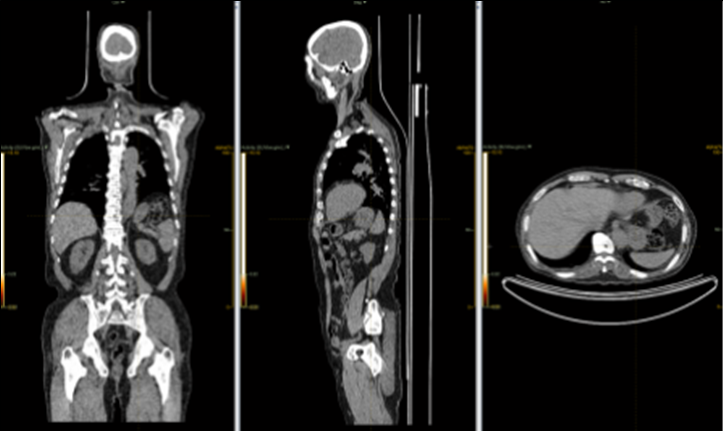

4) 실제 예시

| 폐암 | 혈액암 | 정상인 |

|---|---|---|

![]() |